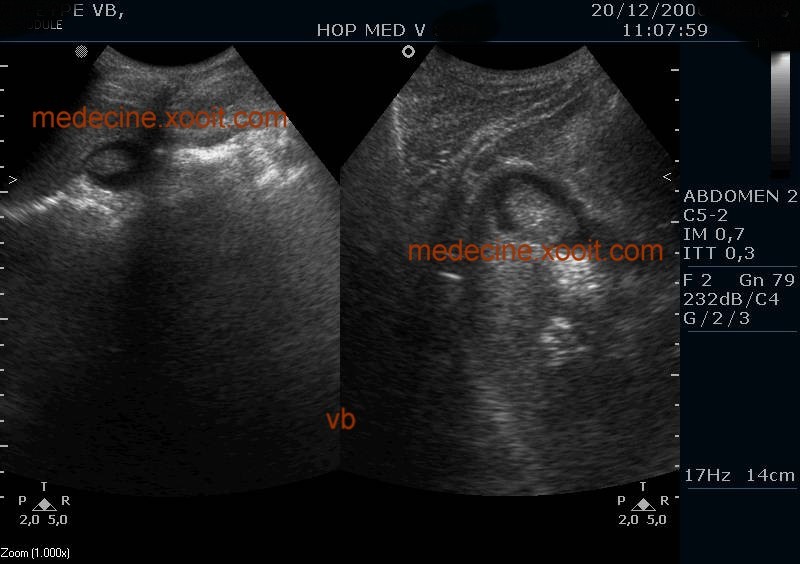

4. En médecine, un polype est une croissance anormale de tissus en saillie (adénome), ou tumeur bénigne, se développant sur les muqueuses. Certains sont plats (polypes sessiles), d'autres possèdent un pied plus ou moins long (polypes pédiculés).